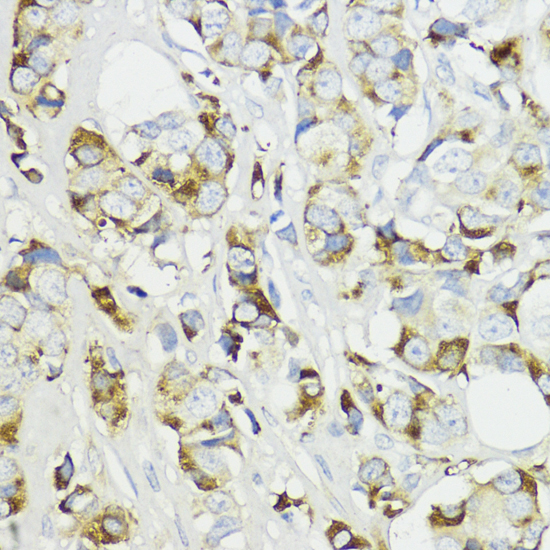

Immunohistochemistry of paraffin-embedded human mammary cancer using Complement Factor B antibody.